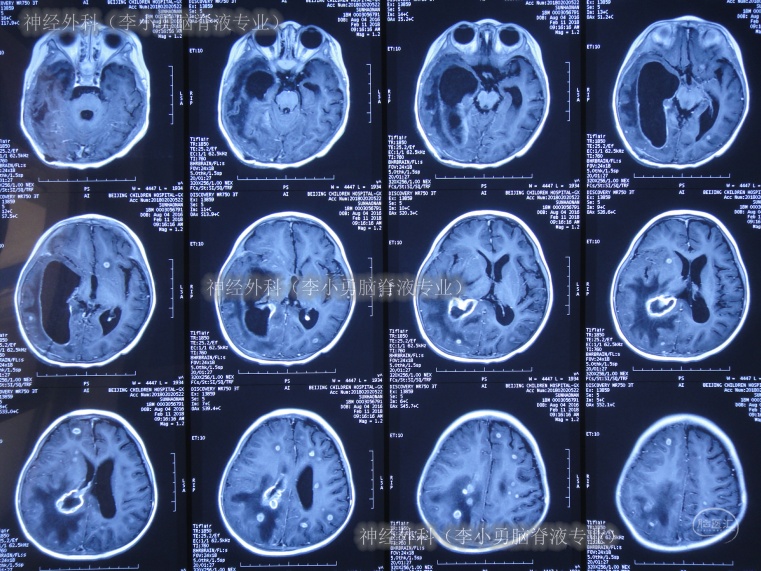

2018年2月7日(第3家医院治疗8天),查头部血管造影示未见异常(图-3);查头MRI示右侧脑室扩张,脑室积脓,中线左移,大脑多发环状异常信号(图-4)。

图-3:2018年2月7日头部血管造影

图-4:2018年2月7日头部MRI